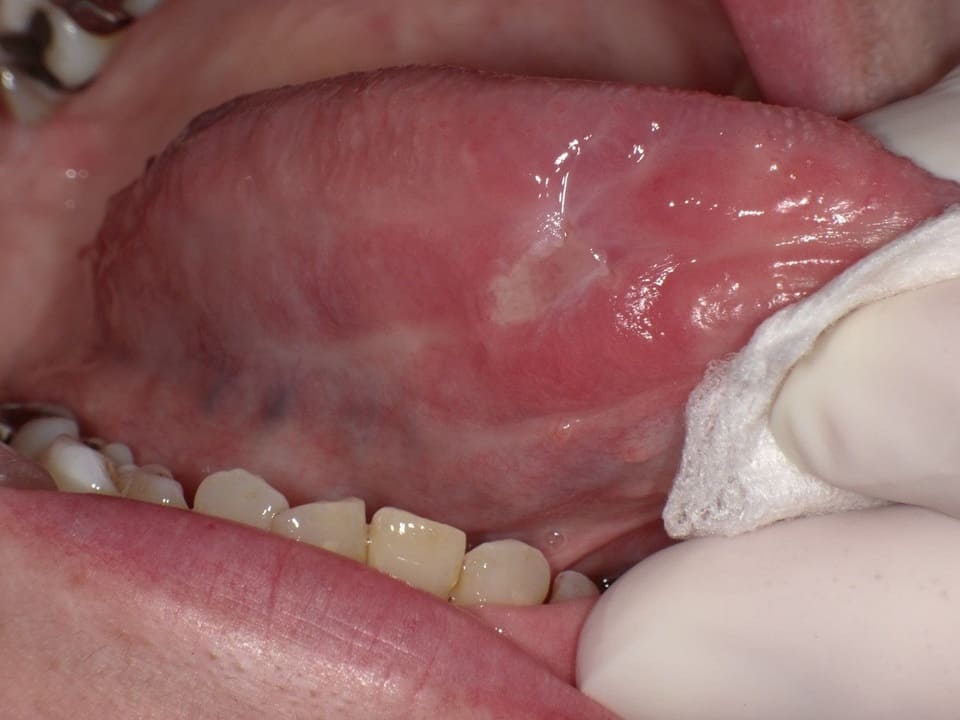

舌の白い点は口内炎?舌がんと見分けるポイントをご紹介! – ココシカ。

こんな症状が実は病気のサイン?:口腔内の異変と早期発見・治療の重要性口腔がん検診・舌がん検診予約を歯科医院で一般社団法人口腔がん撲滅委員会。

舌の口内炎はがんの可能性?舌がんと口内炎の見分け方や治療方法を解説 - 口腔外科DOC。